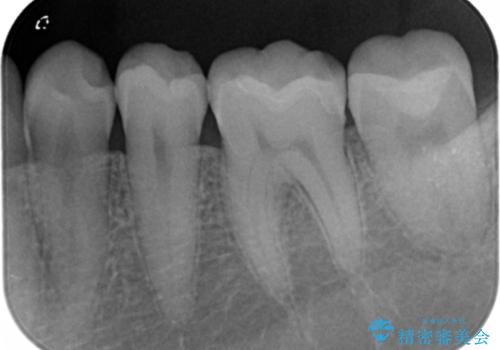

セラミックでの治療を希望されたため、詰められている樹脂の材料を除去してからセラミックインレーでの修復を行いました。

- 左下67 セラミックインレー 77000円×2本費用は治療当時の料金となります

クラウンタイプに比べ歯を削る量を抑えられ、白いセラミックインレーでの修復ができたことに大変喜んでいただけました。

ナイトガードも毎日使用され定期的にメンテナンスにも通っていただいていることもあり、現在セラミックインレー・歯質に特に問題はなく快適に過ごされているそうです。